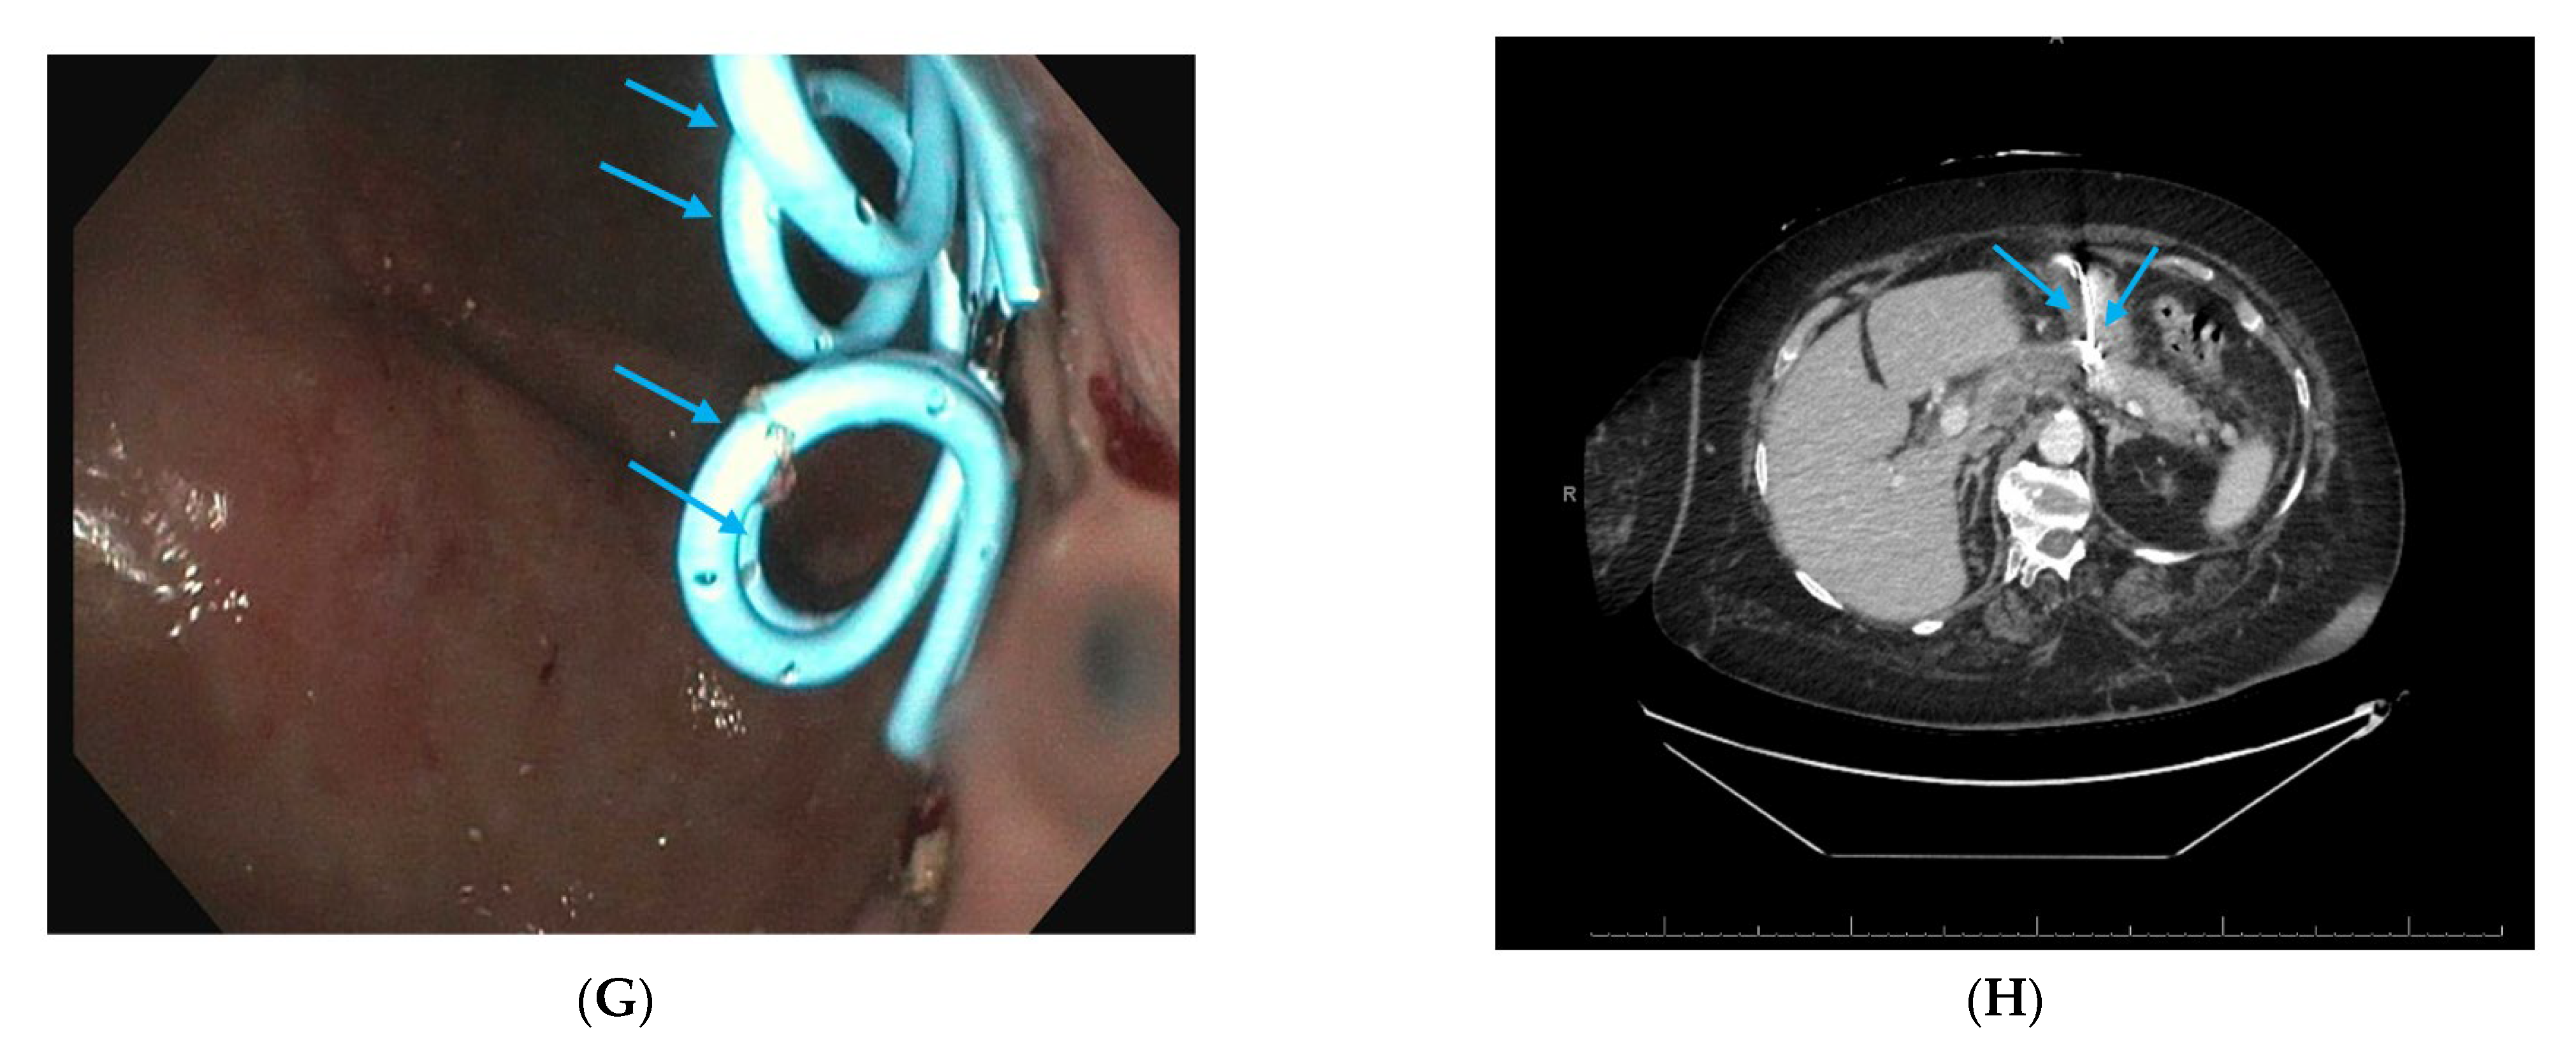

2.7. Interventional Radiology-Guided Embolization of Pseudoaneurysms

2.8. Pancreatic Fistula Treatment

2.9. Approach to Disconnected Pancreatic Duct Syndrome (DPDS) After Severe Pancreatitis